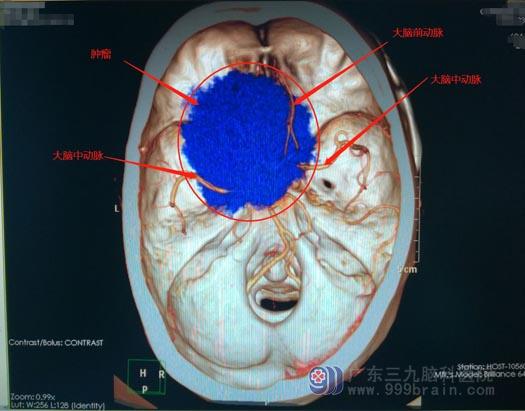

包绕多条颅内动脉的蝶骨嵴巨大脑膜瘤

入住神经外五科后,进一步的影像检查证实石先生是“蝶骨嵴巨大脑膜瘤”,肿瘤巨大,并且包绕了左侧颈内动脉、大脑前、大脑中动脉。

▲术前CTA

肿瘤巨大,不但压迫了周围重要的脑组织结构,还包绕了多条颅内动脉及其分支,肿瘤血运特别丰富加上颅内压增高等不利因素,手术全切相当因难,如果不能全切肿瘤,那瘤区的出血将不可想象。手术风险巨大,手术全切肿瘤并保留最佳神经功能是神经外科医生面临的极大挑战。

医院副院长、神经外五科主任带领团队针对患者病情、结合检查结果进行了详细的讨论。先DSA造影,查看颅内血管情况和肿瘤供血动脉,并行球囊压迫实验和allen实验(用于检查侧支循环和尺动脉通畅与否),为术中颅内大血管损伤做搭桥准备。术前准备妥当后,由鲁明主刀实施“左侧蝶骨嵴巨大脑膜瘤术”;术中见病变范围约为6.3cm×6.0cm×5.2cm,病变部分包绕左侧颈内动脉、双侧大脑前动脉、左侧大脑中动脉及左侧视神经等重要结构;将肿瘤全部切除,术中颈内动脉、大脑前动脉、大脑中动脉及视神经保护良好,术中出血约400ml。